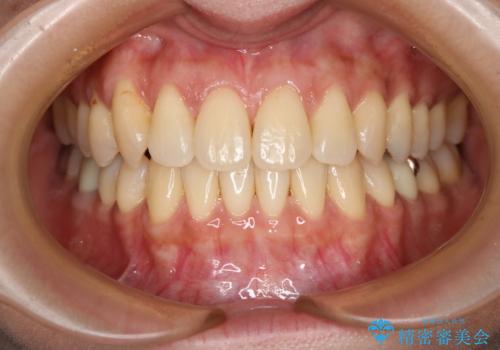

前歯が内側に入っている:インビザライン治療

- 上の前歯は内側に入っていることが気になりご相談にいらした方です。インビザラインにて治療を行いました。

1週間でのマウスピース交換を指示していましたが、20時間以上使えない時があると不安との事で、2週間ごとの交換にしていました(実際はほとんど20時間以上使用できていたようです)。治療終了まで時間はかかりましたが、最終的に綺麗に並べることができ、大変喜んでいただけました。